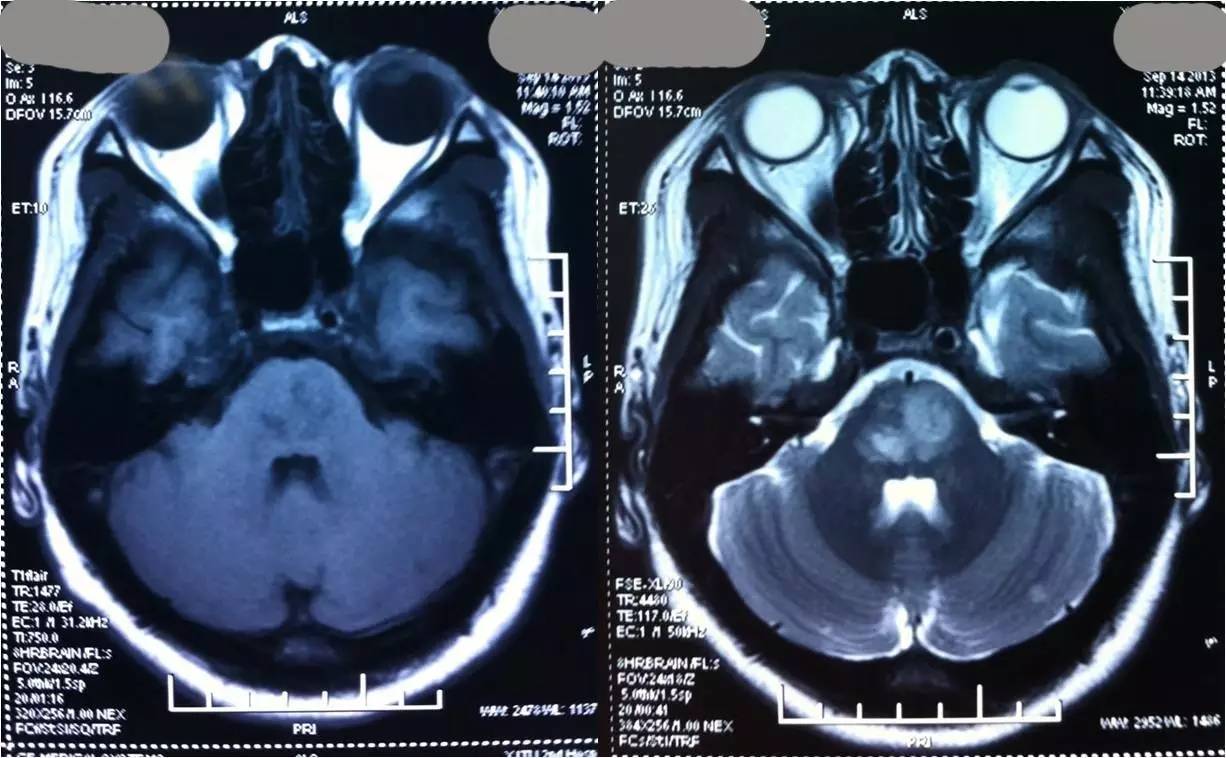

术前

3